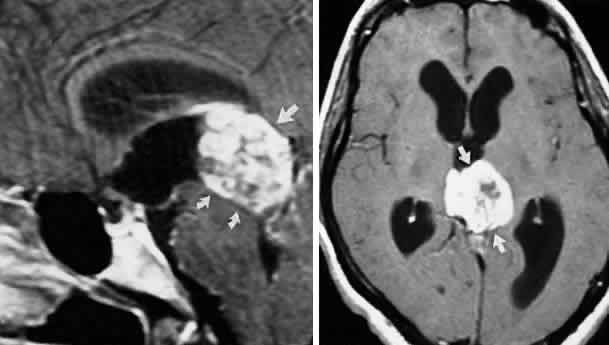

Acquired bi-nuclear total ophthalmoplegia is occasionally seen (Fig. 11), as reported by Masucci.82 These findings are the result of thrombotic or embolic processes at the level of the basilar bifurcation, with occlusion of the median mesencephalic perforating arteries. Congenital bilateral total ophthalmoplegia with or without levator and pupil sparing has been reported and may be associated with dysplasia of the corpus callosum.83

Fig. 11. Bilateral oculomotor palsies (nuclear?) associated with abrupt onset of vertigo and mild left hemiparesis.

Primary neurinoma of the oculomotor nerve is a relatively rare lesion that should be considered in children or young adults with insidious third nerve palsy. These may occur in the cavernous or interpeduncular portion of the nerve (Fig. 13).99,100

Fig. 13. Insidiously progressive third nerve palsy due to oculomotor neurinoma (arrows) in 16-year-old girl. MRI T-1, enhanced axial (top) and coronal (bottom) sections.